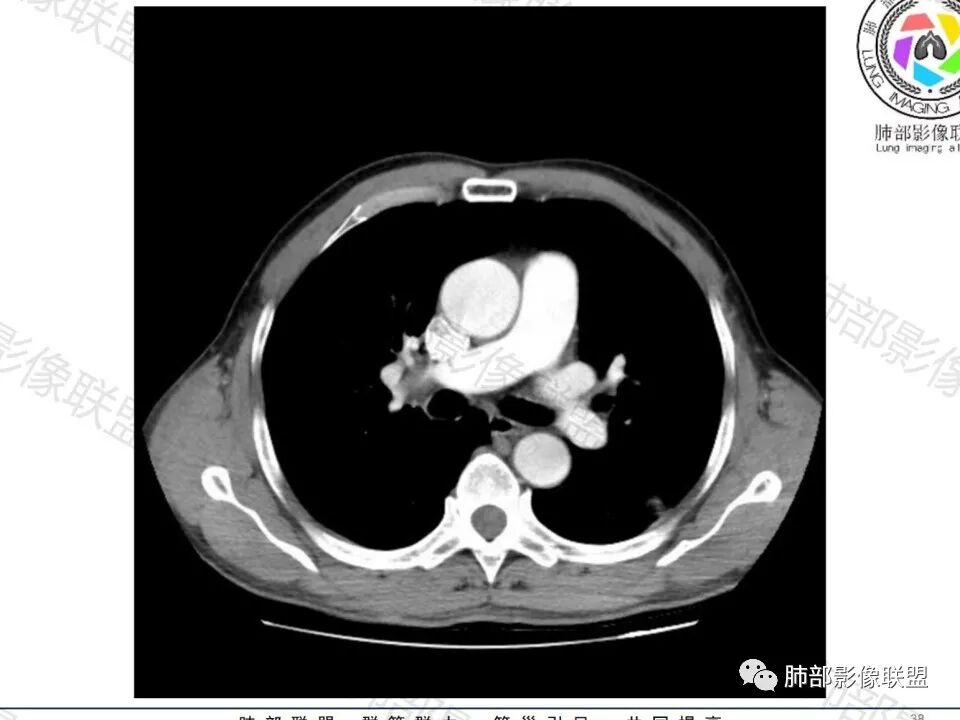

这枚结节的纵隔窗在没有调节窗位的情况下,已经很密实了,说明这个结节里面是软组织的成分,这与普通炎性结节(隐球菌等)的密度还是有区别的,很多年前就有人提出,纵隔窗显示越大,恶性可能越大;

结节周围有磨玻璃影,边界似清不清的,但是总体不如炎性晕征那么模糊;

增强的程度很难讲,但是不均匀强化是可以确定的;

有收缩力,但是很轻,按照常理,实性结节因为有占位效应,不太会有收缩力,但是叶间胸膜有凹陷。所以讲,这个结节还是开了放心。